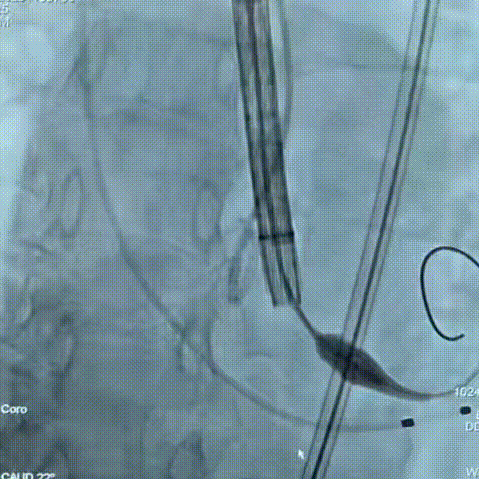

手术过程:在右股动脉穿刺建立通路后,顺利送入大鞘,经食道超声及血管造影确认路径稳定。18mm球囊预扩后评估冠脉灌注良好,后将Prostyle A® AV26瓣膜精准释放于目标位置,超声显示无瓣周漏,术后即刻造影显示无明显反流,术前PGmean40mmHg,术后导管测平均跨瓣压差8mmHg,心功能明显改善,患者生命体征平稳。

最终造影形态位置良好,无瓣周漏

平衡径向支撑力:该患者为Type1型二叶瓣,Prostyle A植入后功能区呈现较好的形态,狭窄撑开的同时保证了较好的EOA,避免因瓣口形态不匹配引发的术后跨瓣压差残留、瓣叶活动受限等血流动力学异常问题;

优异的过弓性能:该患者横位心患者,自膨瓣中的短瓣架设计助力过弓性能,术中无需snare,丝滑操作到位,表现优异;